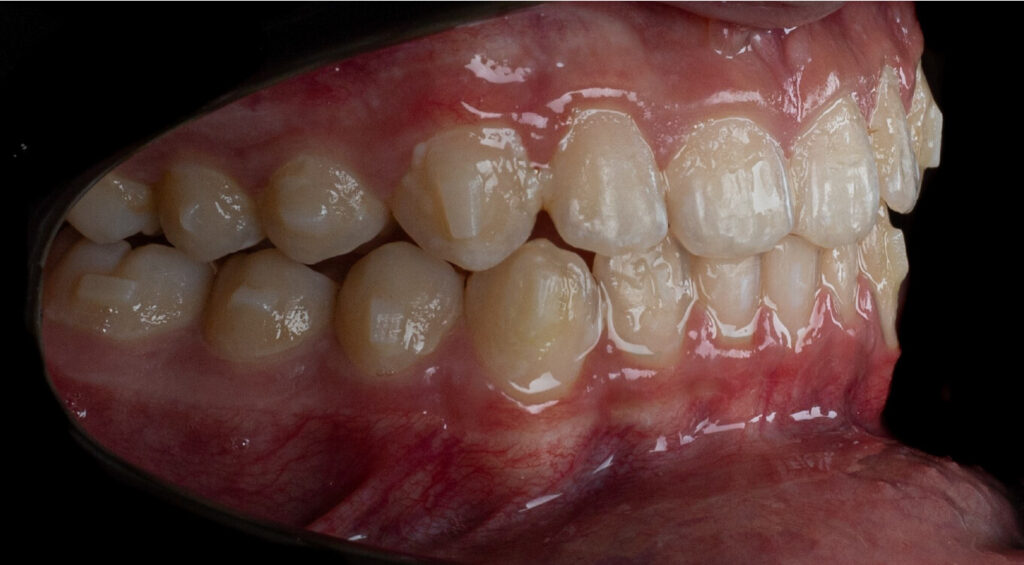

Um paciente do sexo masculino, com 13 anos de idade, apresentou-se com uma mordida profunda, caracterizada pela cobertura quase completa dos incisivos mandibulares. A avaliação clínica revelou apinhamento em ambas as arcadas, rotações dentárias e proclinação dos incisivos laterais superiores, contribuindo para as preocupações estéticas do paciente. O perfil facial era retrusivo, consistente com retrognatismo mandibular, e não foram detectadas anomalias periodontais significativas.

O paciente apresentava uma relação esquelética de Classe II com molares e caninos bilaterais em Classe II e um padrão dentário de Classe II divisão 2. A mordida profunda estava associada a um apinhamento anteroinferior e a uma curva de Spee acentuada. A análise facial revelou boa simetria, um terço facial inferior ligeiramente aumentado e um perfil convexo caracterizado por retrusão mandibular e do mento. A competência labial estava ligeiramente reduzida, com diminuição do ângulo nasolabial e leve tensão do músculo mentoniano, fatores que comprometiam a harmonia facial global.